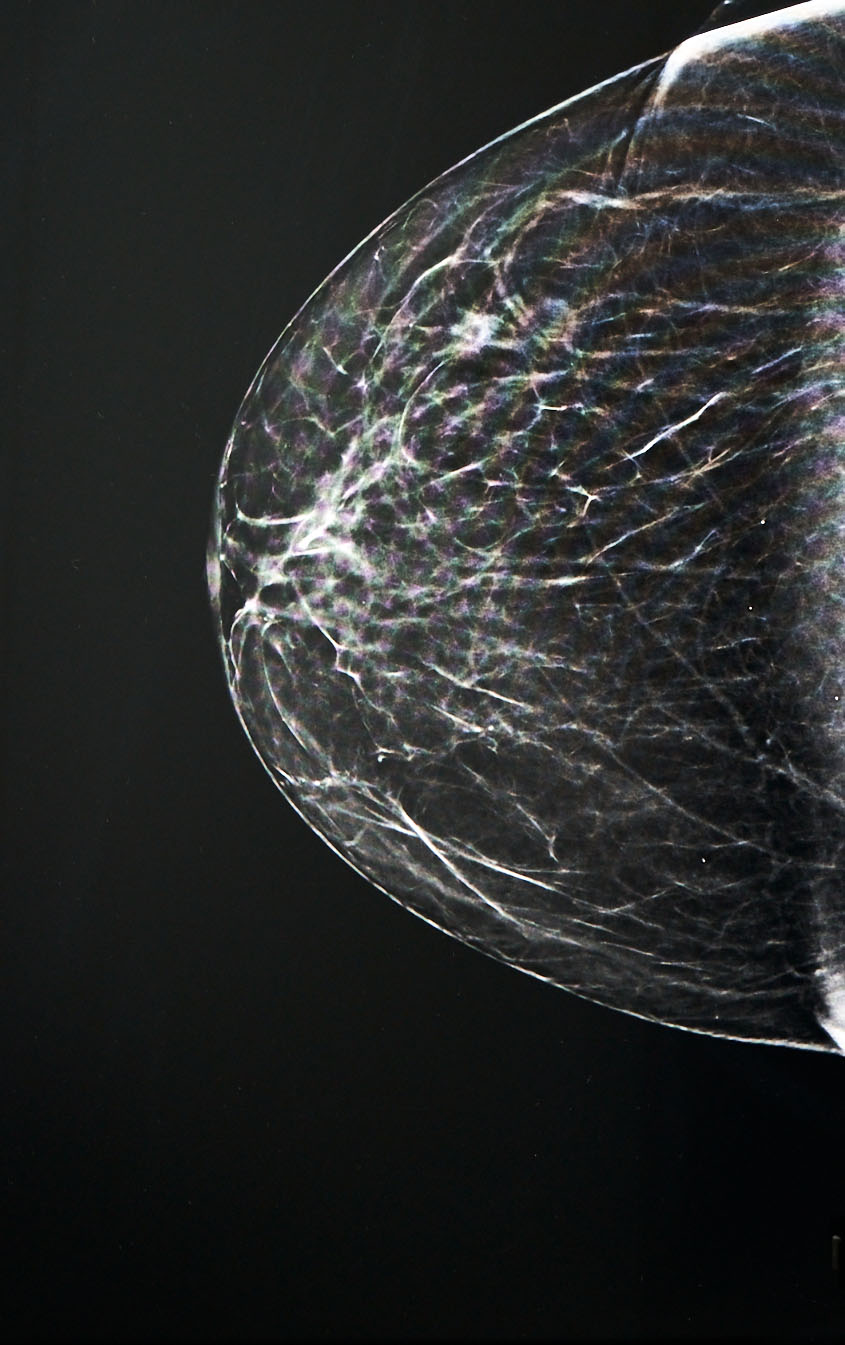

Presso il nostro studio, siamo impegnati a offrire servizi di senologia all'avanguardia che integrano tecnologia di punta e una forte enfasi sulla prevenzione. Riconosciamo l'importanza cruciale dello screening mammografico al fine di individuare precocemente le potenziali minacce al benessere del seno. Uno dei nostri strumenti più recenti è il modernissimo mammografo 3D, che rappresenta un passo avanti significativo nella diagnostica del seno.

Il nostro mammografo 3Dimensions™ HOLOGIC è in grado di effettuare una tomosintesi mammaria in alta risoluzione in soli 3,7 secondi, garantendo il massimo comfort per la paziente. Questa tecnologia non solo riduce notevolmente il tempo di compressione del seno, migliorando il comfort, ma offre anche una maggiore precisione diagnostica rispetto alla mammografia convenzionale 2D.

Uno dei vantaggi più significativi del nostro sistema mammografico 3D è la sua capacità di individuare una percentuale significativamente maggiore di tumori invasivi della mammella rispetto alla sola mammografia 2D, con un incremento che va dal 20% al 65%. Questo significa che possiamo rilevare precocemente le potenziali minacce e adottare misure preventive tempestive.

Inoltre, il sistema di immagini Intelligent C-View integrato nel nostro mammografo consente ai nostri radiologi di individuare dettagli mammografici anche di piccole dimensioni e di analizzare la morfologia delle lesioni in modo rapido e preciso. Questa innovativa tecnologia crea immagini 2D altamente correlate ai dati 3D™, rivelando particolari che potrebbero non emergere in immagini 2D convenzionali.

Ciò è reso possibile grazie all'uso di algoritmi di intelligenza artificiale all'avanguardia che combinano i dati 2D con quelli 3D senza alcuna esposizione aggiuntiva alle radiazioni. Il risultato è una diagnosi più accurata e dettagliata, che contribuisce in modo significativo alla prevenzione e alla salute del seno.